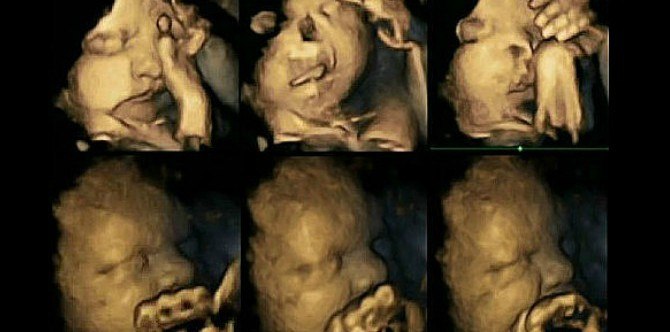

2 baris gambar imbasan ultrasound 4D

Pergerakan janin ibu perokok (atas) dan janin ibu bukan perokok (bawah); Sumber: Dr Nadja Reissland, Universiti Durham

Cuba tengok janin dengan muka berkerut di baris atas. Janin itu seolah-olah menutup mukanya dan mahu “mengelak” sesuatu.

Ibunya merokok sebanyak 14 batang rokok setiap hari. Manakala gambar ultrasound baris kedua menunjukkan janin dalam keadaan tenang. Ibunya bukan seorang perokok.

Berdasarkan imbasan ultrasound 4D tersebut, para penyelidik mendapati janin terdedah kepada asap rokok ibu menunjukkan kadar pergerakan mulut yang jauh lebih tinggi daripada kadar pergerakan normal janin.